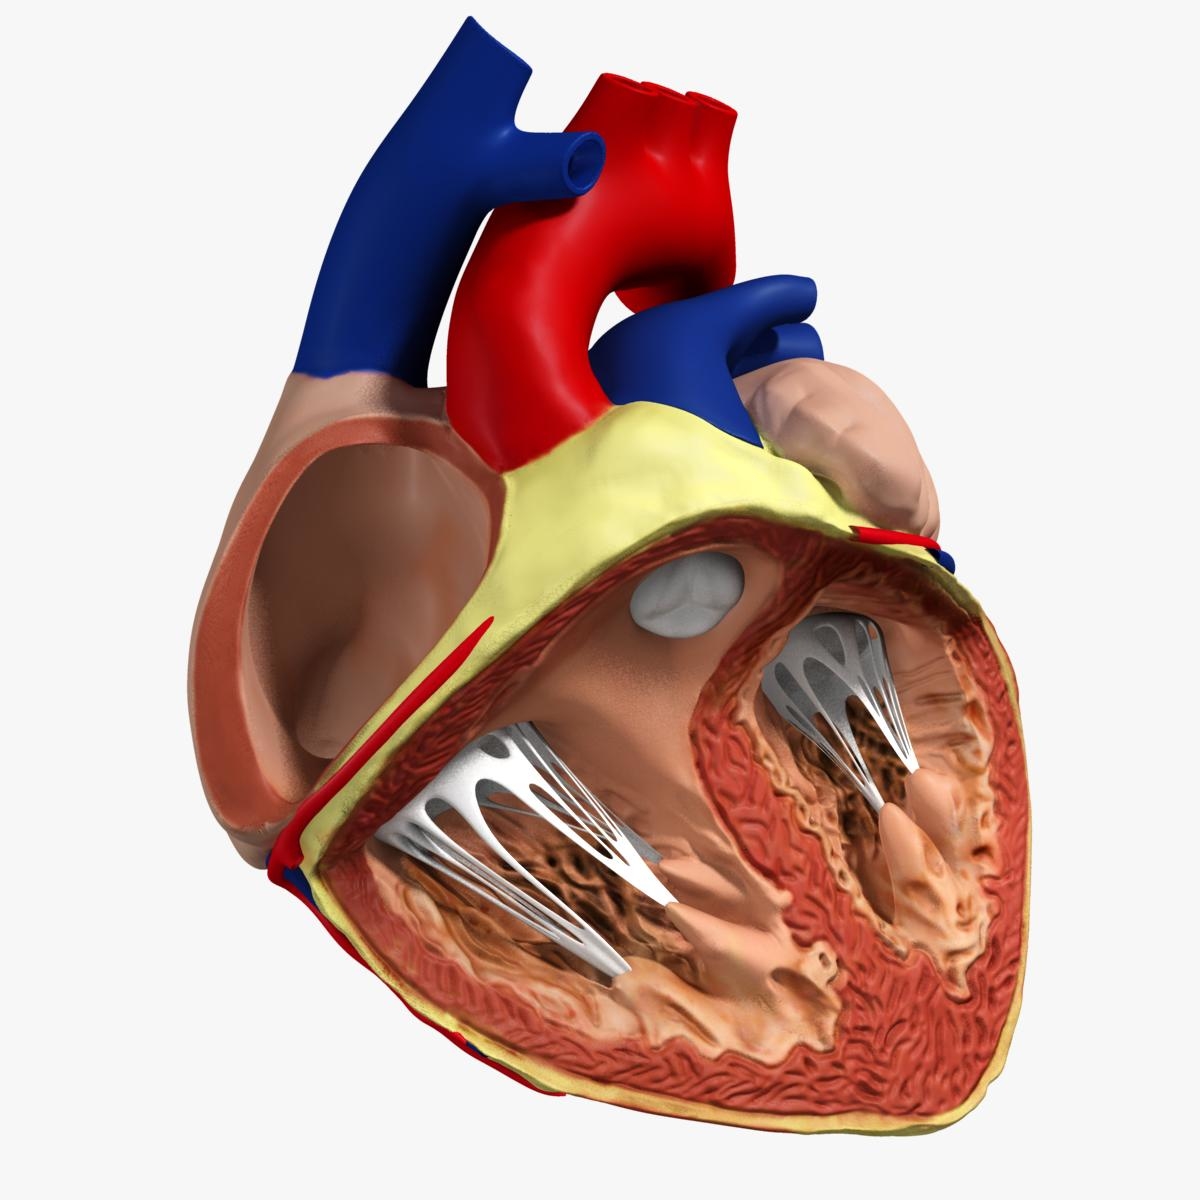

anatomy human heart 3d c4d  Modeled human heart section 3D model - TurboSquid 1657004

Modeled human heart section 3D model - TurboSquid 1657004  Heart by Rustamova on @DeviantArt | Anatomical heart art, Anatomy art, Heart drawing

Human Heart Section 3D model | CGTrader  human heart - internal anatomy 3d model

Human Heart Cutaway Anatomy 3D model section | CGTrader  Human Heart by Mutantenmaid on DeviantArt